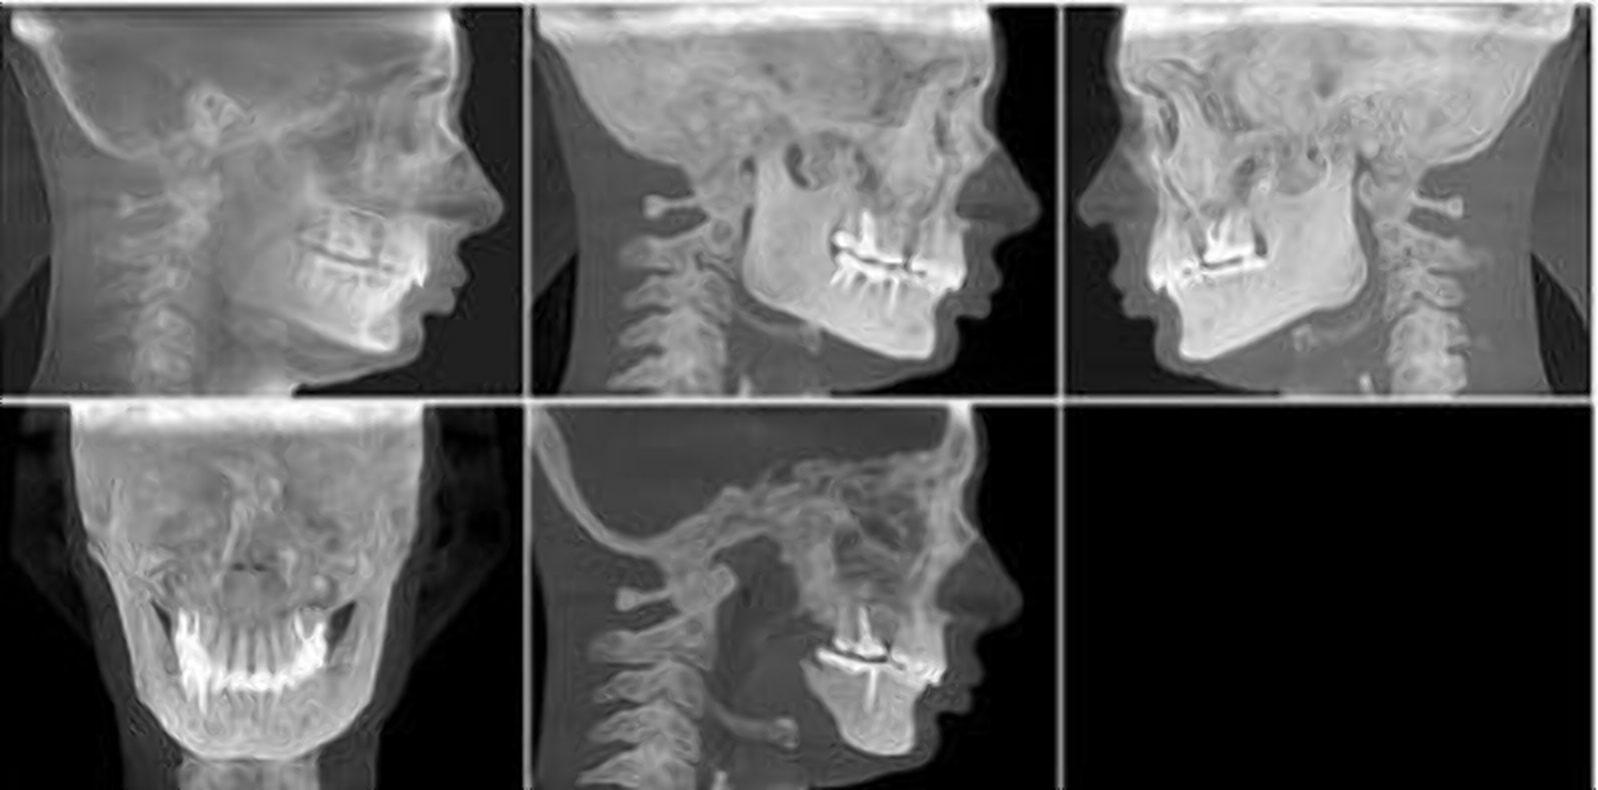

Что было бы с улыбкой Фредди Меркьюри, если бы он обратился к ортодонту

2024-08-06 в 7:00, admin, рубрики: здоровье, зубы, клиника, полиодонтия, прикус, стоматология, челюсть

То есть, даже если по какой-то причине эстетика не волнует человека, то скученность зубов функционально мешает гигиене и сокращает срок их жизни, а нижние зубы постоянно бьются о верхние и вывихивают их ещё сильнее.

Впрочем, девушку, которая пришла ко мне в ноябре 2020 года, когда я ещё работала в другой клинике, больше всего волновала как раз-таки именно эстетика: с такими зубами она стеснялась открывать рот и не могла сомкнуть губы. Главный её запрос звучал так: «Светлана, сделайте мне, пожалуйста, красиво!»

Ну что ж, я сделала. Стоило это около 600 тысяч, лечение заняло чуть меньше трёх лет. Но результат того стоил!